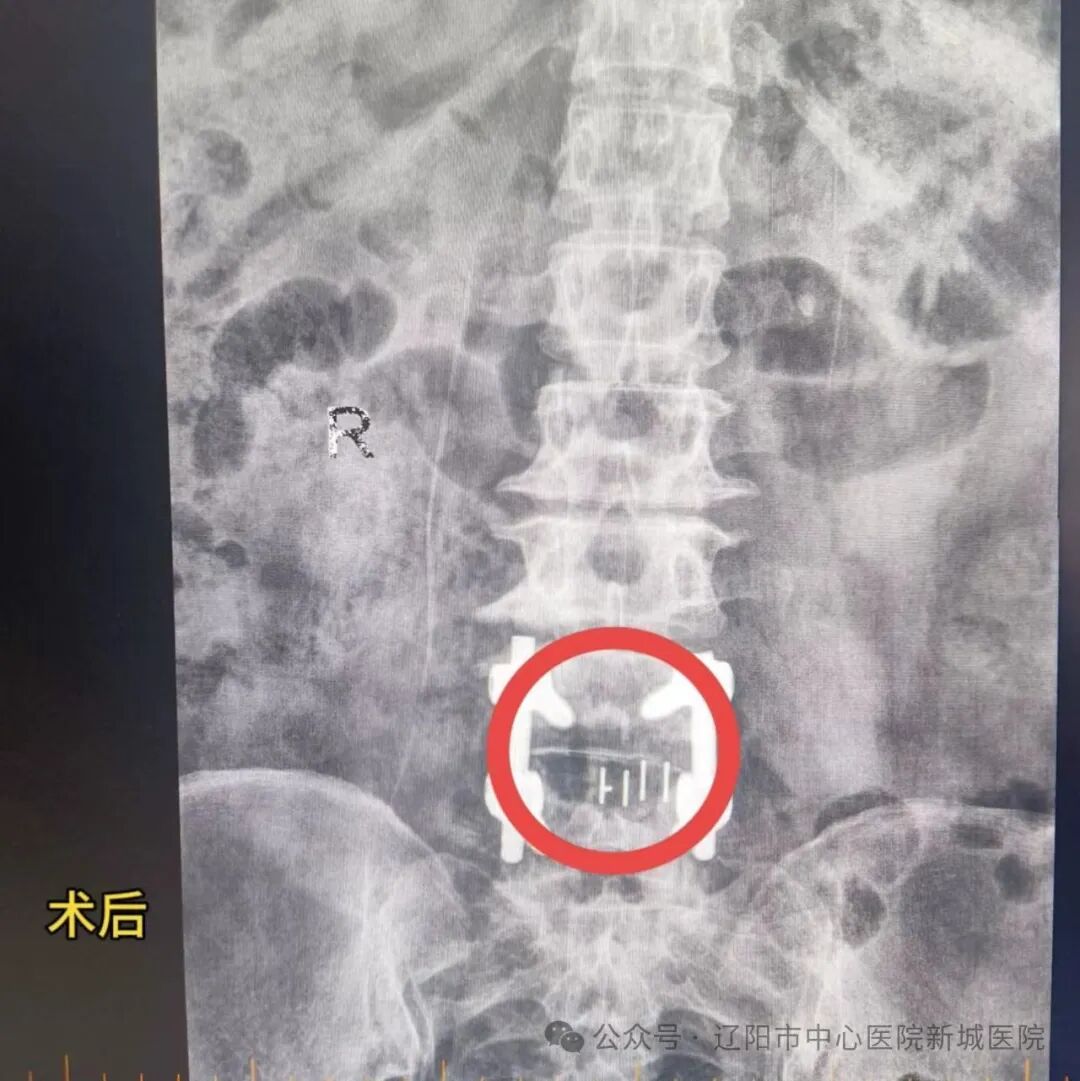

2024年11月1日,在麻醉科和手術(shù)室的密切配合下,楊教授帶領(lǐng)醫(yī)療團(tuán)隊(duì)為王先生進(jìn)行了椎管內(nèi)麻醉下的腰椎間盤(pán)摘除、椎管擴(kuò)大成型術(shù)。術(shù)中見(jiàn)腰椎管狹窄明顯,“馬尾”神經(jīng)受壓嚴(yán)重,于是進(jìn)行受壓神經(jīng)根的廣泛減壓,取出髓核,固定腰椎。手術(shù)過(guò)程非常順利,術(shù)野出血量很少,術(shù)后王先生安返病房。

術(shù)后第二日,王先生自覺(jué)腿的疼痛完全消失,麻木癥狀較之前緩解了很多,可簡(jiǎn)單的自主活動(dòng),活動(dòng)度也比術(shù)前有明顯的改善;術(shù)后第三日,麻木癥狀基本消失,已下床行走;術(shù)后第五日出院回家康復(fù)休養(yǎng)。